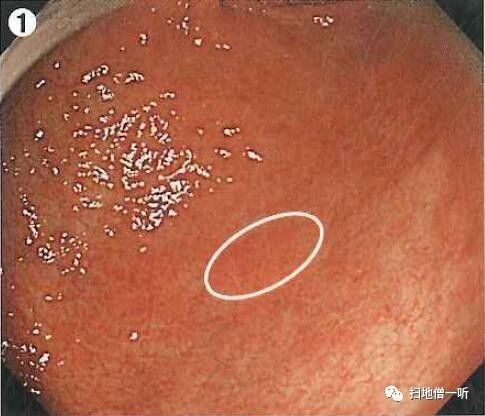

Q:胃癌在何处?

提示:请注意粘膜凸凹的变化。

A:胃癌在图1。HP现症感染胃癌。

背景粘膜为O-1型萎缩。胃窦大弯前壁可见一中央凹陷周边隆起性病变。考虑为IIC型病变伴周围反应性隆起。

靠近观察可见凹陷面周围确有隆起。随蠕动动态观察正面观可见凹陷面呈棘状或蚕食状(黄圈部分)高度怀疑高分化腺癌。

靛胭脂染色后凹陷面界限更加清晰,周围隆起部分粘膜同周围背景粘膜,故为反应性隆起的非癌粘膜。

最终诊断:胃窦大弯前壁,O-IIc,5mm,tub1,T1a(M),UL(-)

小结:背景粘膜判断有无HP感染

反应性隆起常见于胃癌

蚕食像应高度怀疑胃癌

补充:胃体部均一的发红粘膜、糜烂性发红、大弯粘膜肿胀蛇形、粘膜不易冲洗等均提示HP感染。

对照下图为HP阴性的大弯粘膜表现。